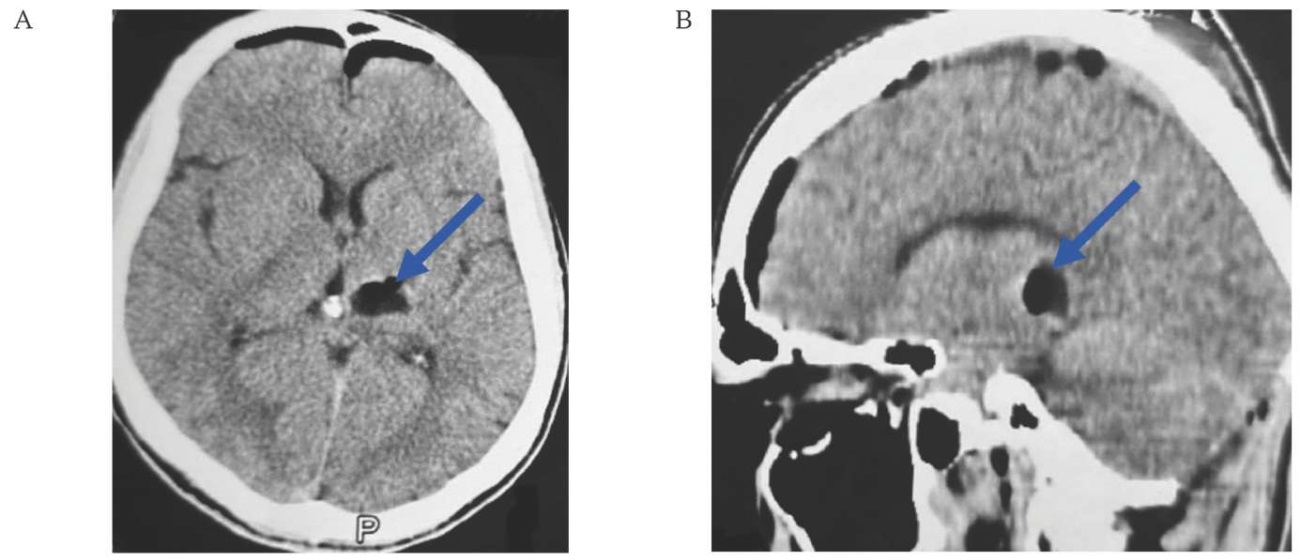

Контрольная КТ в послеоперационном периоде проведена на третьи сутки, по данным исследования: состояние после медианной субоксипитальной краниотомии, остаточной каверномы и повторного кровоизлияния не выявлено (рис. 4A, B).

РИС. 4. Компьютерная томография пациента 38 лет на 4-й день после удаления кавернозной мальформации в дорсальной части левой ножки среднего мозга (01.06.2024).

A. Аксиальный срез: кавернома с капсулой гематомы полностью резецирована (стрелка).

В. Сагиттальный срез: кавернома с капсулой гематомы полностью резецирована (стрелка).